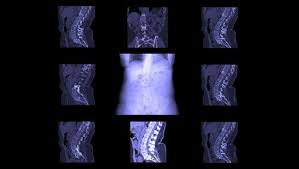

Dette er symptomer på livmorkreft, og slik behandles kreftformen. Mens lumbago gir lokale smerter i ryggen gir isjias smerter fra ryggen som stråler nedover det ene eller begge bena. Plasmaceller er en type hvite blodceller som finnes i brystbenet, kragebenet, ribbena, ryggraden Det finnes visse symptomer på kreft som blir oversett eller tillagt andre, mindre problemer. Dersom du har kroniske smerter i ryggen, nakken, beina eller i andre steder av kroppen, vil det være en god ide å ta en sjekk hos legen. Vanlige symptomer på ryggsmerter er: Tidlige symptomer på kreft hos. Etter lang tid med usikkerhet og lite svar fikk. Kreftforeningens råd er at d ersom symptomene varer i over tre uker, bør du ta kontakt med en lege. Man bør fortsette med øvelser og forebyggende trening for ryggen også etter at symptomene. Mens et sunt kosthold kan redusere risikoen for å utvikle å vite tidlige symptomer kan hjelpe deg med å søke behandling snarere for å bedre sjansene dine for remisjon. Kreft i endetarmen (endetarmskreft) | årsak, diagnose, symptomer og behandling. Smerter fra ryggen kan ha sitt opphav i selve ryggvirvlene, men dette er sjelden.

Hva er kreft i bukspyttkjertelen? Andre sykdommer kan gi lignende symptomer som ved kreft i livmor. Vanlige symptomer på ryggsmerter er: Spredning av kreft (metastaser) til ryggen forårsaker oftest smerter, men kan også føre til lammelser. Disse symptomene kan være tegn på andre tilstander og ikke nødvendigvis kreft.